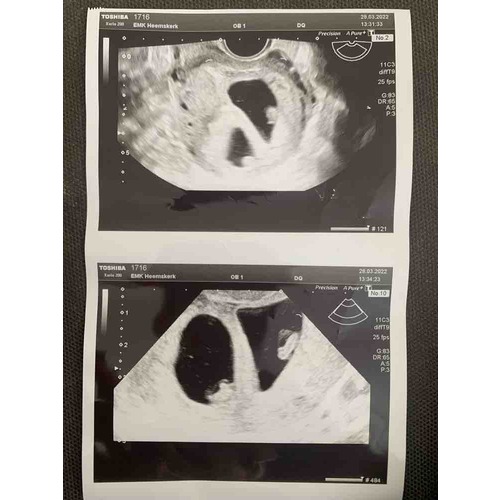

Vandaag eerste echo gehad. Ben 6 weken. Tot mijn verbazing zijn het 2 vruchtzakjes. Bij 1tje het hartje zien kloppen. Bij de andere nog niet. Maandag mag ik terug 馃グ

Hier ook een tweeling, dacht 8 weken te zijn maar is 6+5 nog super klein, maar beide hartjes waren al kloppend te zien